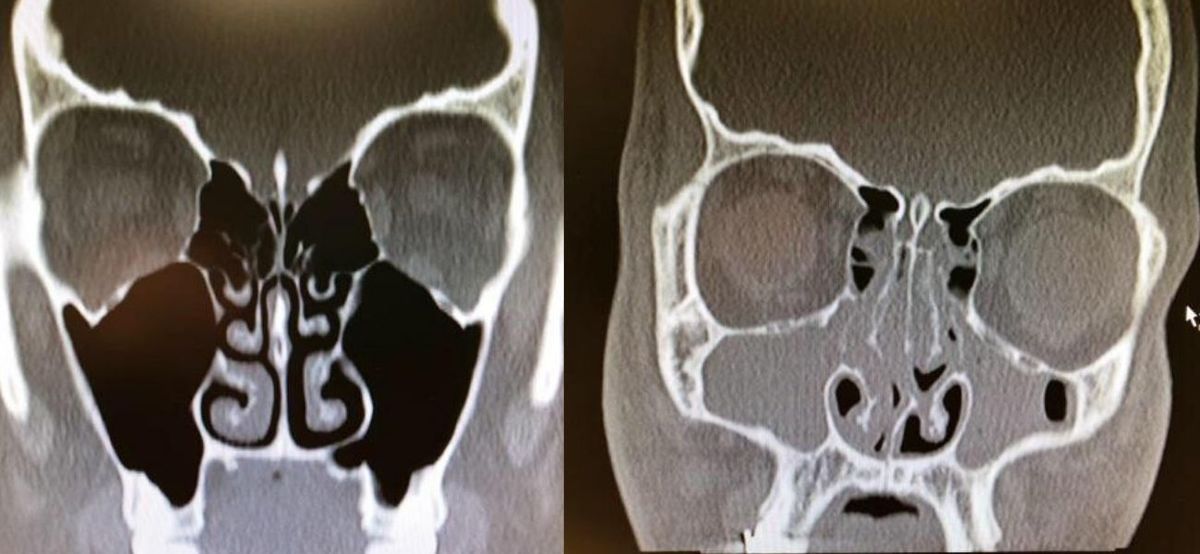

Xrays Of Congested And Un-congested Sinuses Will Make You Grateful For Air

This is really wild. This person had bad congestion and allergies so their sinuses were completely swelled up.

If this doesn’t make you breathe a little easier then I don’t know what will because I am feeling thankful for my un-congested sinuses right now.